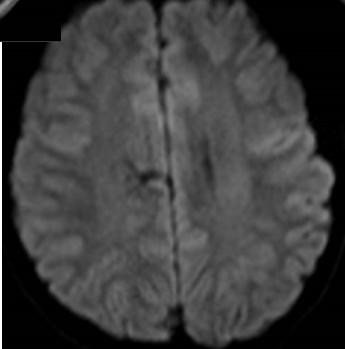

补充图片,DWI也证实T2、FLAIR上四脑室、侧脑室似有液平的地方,是积脓。

绿色无坑,充分体现一个临床病例的特点,急性起病,发烧,神经功能缺损。影像上脑室增大,T2、FLAIR上四脑室似有积脓,室管膜高信号。很多人都猜对了。

也是发烧,病程稍长。但影像上比较典型,T2、FLAIR高信号的地方,DWI也是高信号,提示脓肿。如果配上增强扫描就更理想了。病史中一是发热,二是有免疫抑制的因素,也提示感染性疾病。